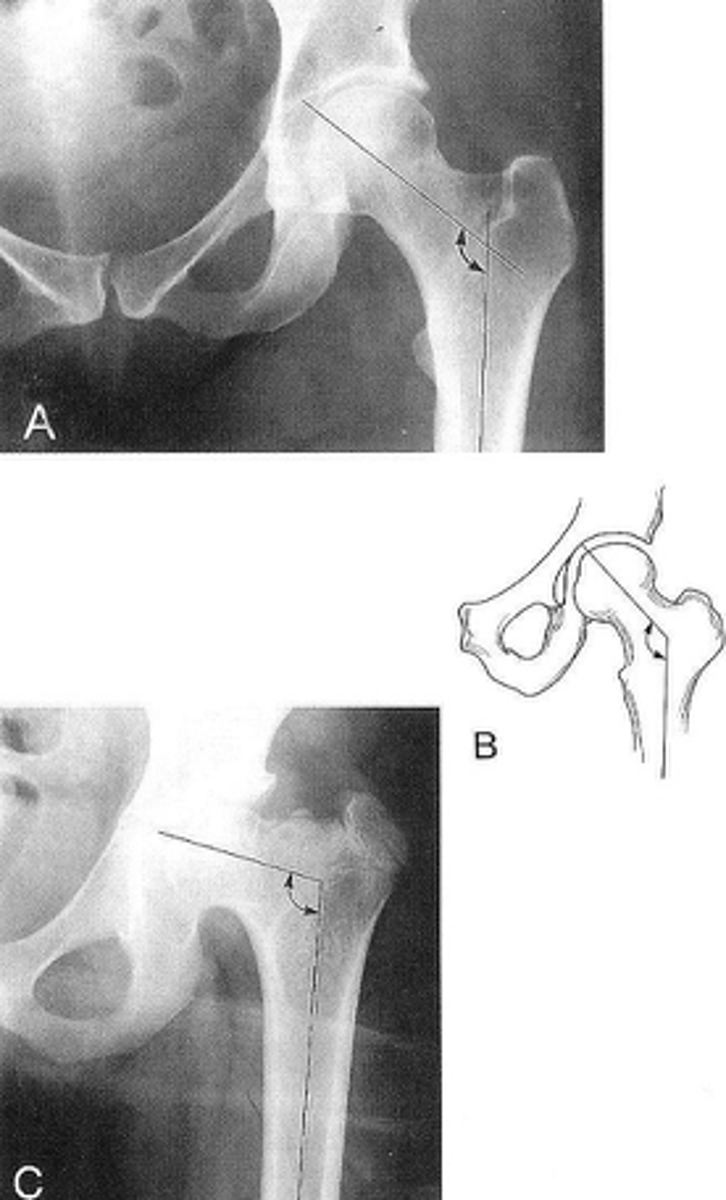

Shenton's line

ID measurement

<p>ID measurement</p>

- AP hip

- AP pelvis

What views are used to see Shenton's line?

- Smooth arc along femoral neck

- Obturator foramen

Shenton's line landmarks

Continuous and smooth

Shenton's line normal measurements

<p>Shenton's line normal measurements</p>

- Hip dislocation

- Femoral neck fracture

- Slipped epiphysis

Clinical significance of Shenton's line

<p>Clinical significance of Shenton's line</p>

Femoral angle

What views are used to measure the femoral angle?

- Mid-axis of femoral shaft

- Mid-axis of femoral neck

- Intervening angle

Femoral angle landmarks

120-130˚

Normal femoral angle measurement

<p>Normal femoral angle measurement</p>

Coxa vara

Femoral angle <120˚

<p>Femoral angle &lt;120˚</p>

Coxa valga

Femoral angle >130˚

<p>Femoral angle &gt;130˚</p>

Skinner's line

What views are used to see Skinner's line?

- Right angle tangent to tip of greater trochanter

Skinner's line landmarks

Fovea capitis should lie above or at level of trochanteric line

Skinner's line normal measurement

<p>Skinner's line normal measurement</p>

Fracture or other causes of coxa vara

Clinical significance of Skinner's line

<p>Clinical significance of Skinner's line</p>

Klein's line

What views are used to see Klein's line?

Line along femoral neck

Klein's line landmarks

<p>Klein's line landmarks</p>

Line should intersect portion of femoral head

Klein's line normal measurement

<p>Klein's line normal measurement</p>

Slipped capital femoral epiphysis

Clinical significance of Klein's line

<p>Clinical significance of Klein's line</p>